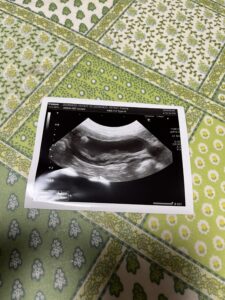

血液検査 尿検査 超音波検査

腎臓結石怪しい所有り

胆嚢異常なし